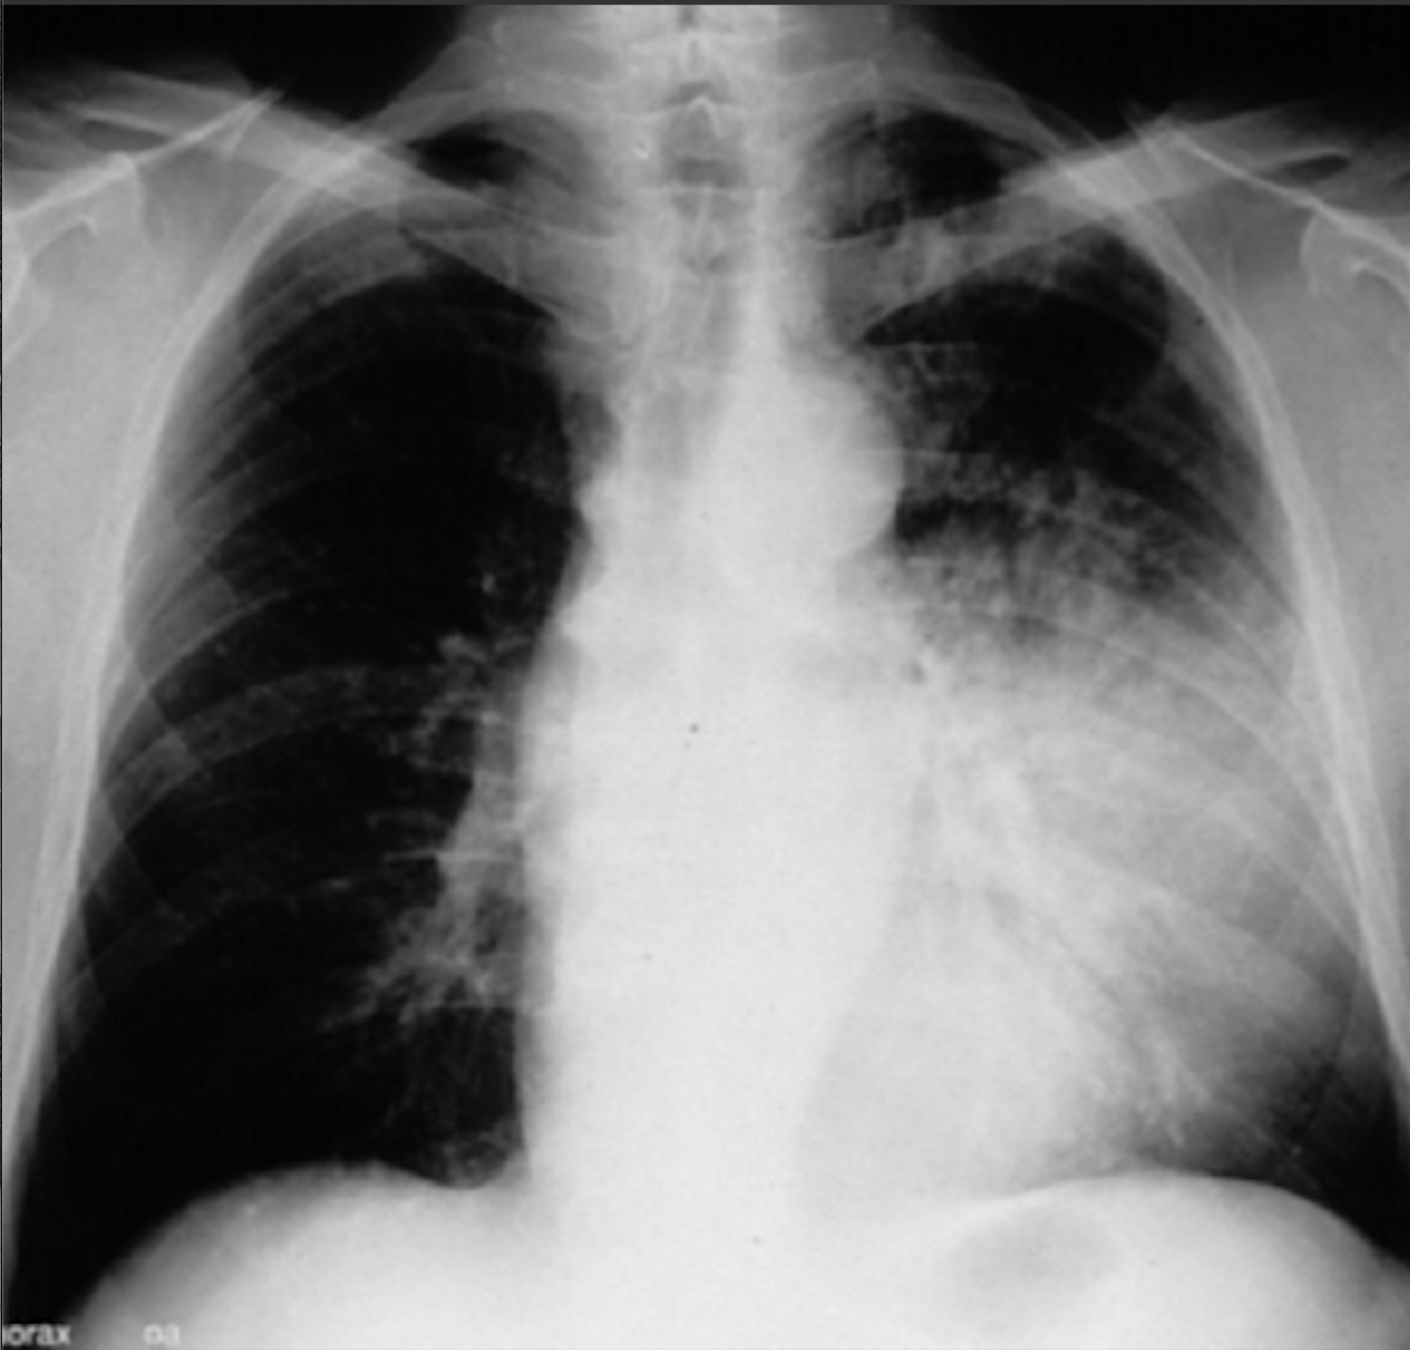

White Out

Left Atrial Enlargment